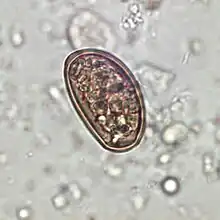

Traditionally, diagnosis for dicrocoeliasis infection involves the identification of Dicrocoelium dendriticum eggs in the faeces of a human or other animal. However, in humans, eggs in the stool may be a result of ingesting raw infected animal liver and may not in fact indicate dicrocoeliasis.[15] Therefore, examining bile or duodenal fluid for eggs is a more accurate diagnostic technique in combination with a liver-free diet.[13]